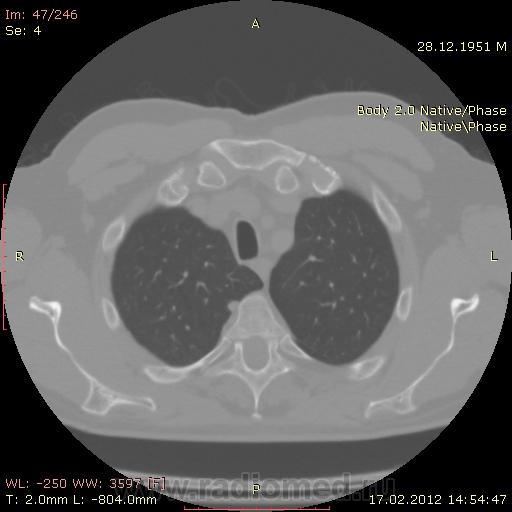

КТ.

На первый взгляд - метастазы. А так, если родственник, искать выходы на МСКТ.

Согласен с Андреем Юрьевичем - наиболее вероятно - это метастазы...исключите первичное новообразование почки.

В феврале 2012 года при очередном флюрографическом обследовании были обнаружены изменения в лёгких. По собственной инициативе было сделано КТ лёгких.

Согласен с коллегами, внешне вылитые метастазы. Но почему нет контраста? Не соли мочевой кислоты точно. Учитывая анамнез можно думать о неопроцессе почек.

Повторяюсь (мнение озвучил еще до КТ и до Ваших коментов) но это отдаленные по времени метастазы рака почки....увы....и даже если будет найден еще один первичный очаг, то все равно это - метастазы...опять - увы....